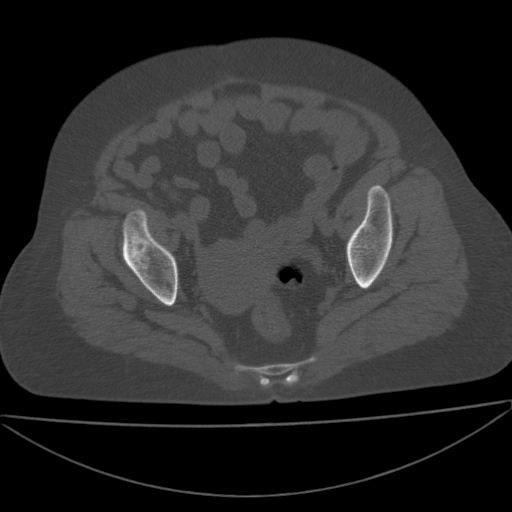

以下是引用王显瑞在2009-4-23 16:45:00的发言:[br]考虑股骨颈陈旧性骨折,股骨头缺血型坏死

以下是引用余辉在2009-4-23 17:08:00的发言:[br]考虑右髋关节退行性变.股骨颈改变考虑陈旧性骨折可能,股骨头顶部关节面下似有透亮区,股骨头皮质环增厚,考虑有股骨头坏死